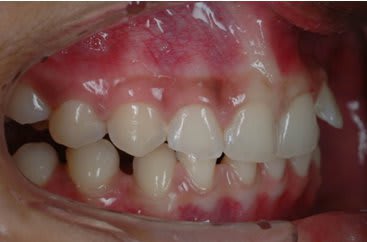

SI joint les photo intra buccal pre traitement et pendant traitement.

Comment expliquer vous le développement ce canting en frontal et de l'open bite en Postérieur ?

Qu'elle est la source du mal ?

Photo 1 on met des brackets et fils un ans plus tard Photo 2

Une seul possibilité a ma connaissance qui explique le canting antérieur et l'open bite postérieur.